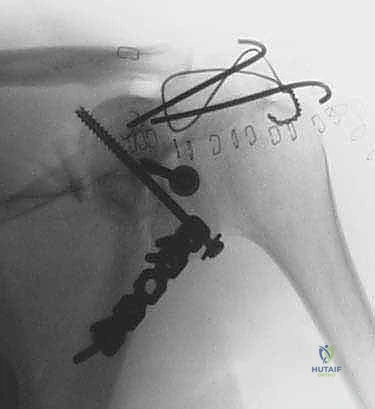

جراحة تثبيت كسور لوح الكتف داخل المفصل: دليل شامل للمرضى مع الأستاذ الدكتور محمد هطيف

تعرف على جراحة تثبيت كسور لوح الكتف داخل المفصل، الأعراض، التشخيص، وخيارات العلاج المتقدمة في صنعاء مع الأستاذ الدكتور محمد هطيف، خبير جراح…